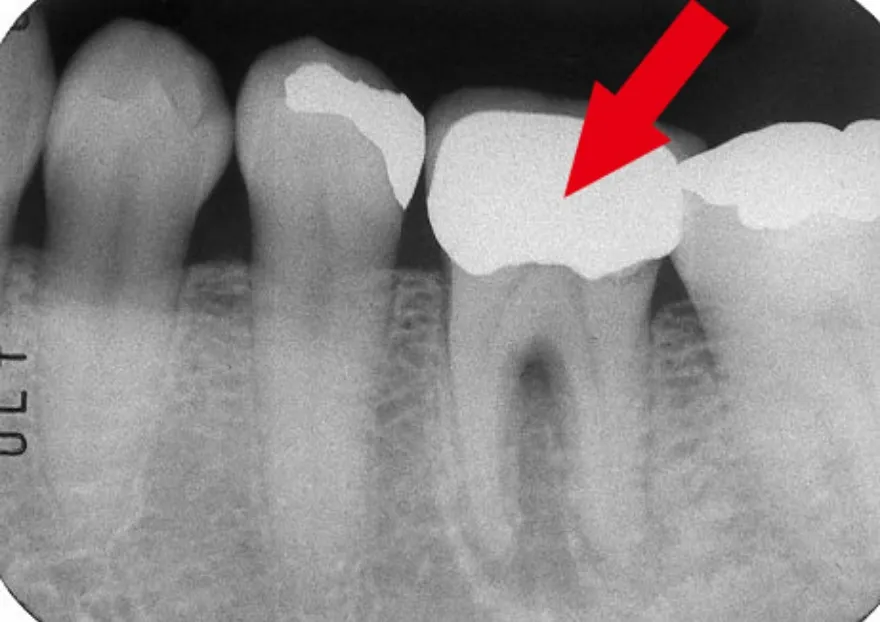

エックス線写真でみる根管治療

• 根管治療前のエックス線写真では、根の先端から股の部分にかけて黒い影が見えます。これが根尖病巣です。

• 根管治療後のエックス線写真では、根の中に詰めた薬剤が白く映っています。根の周りにあった黒い影が消えているのが分かります。